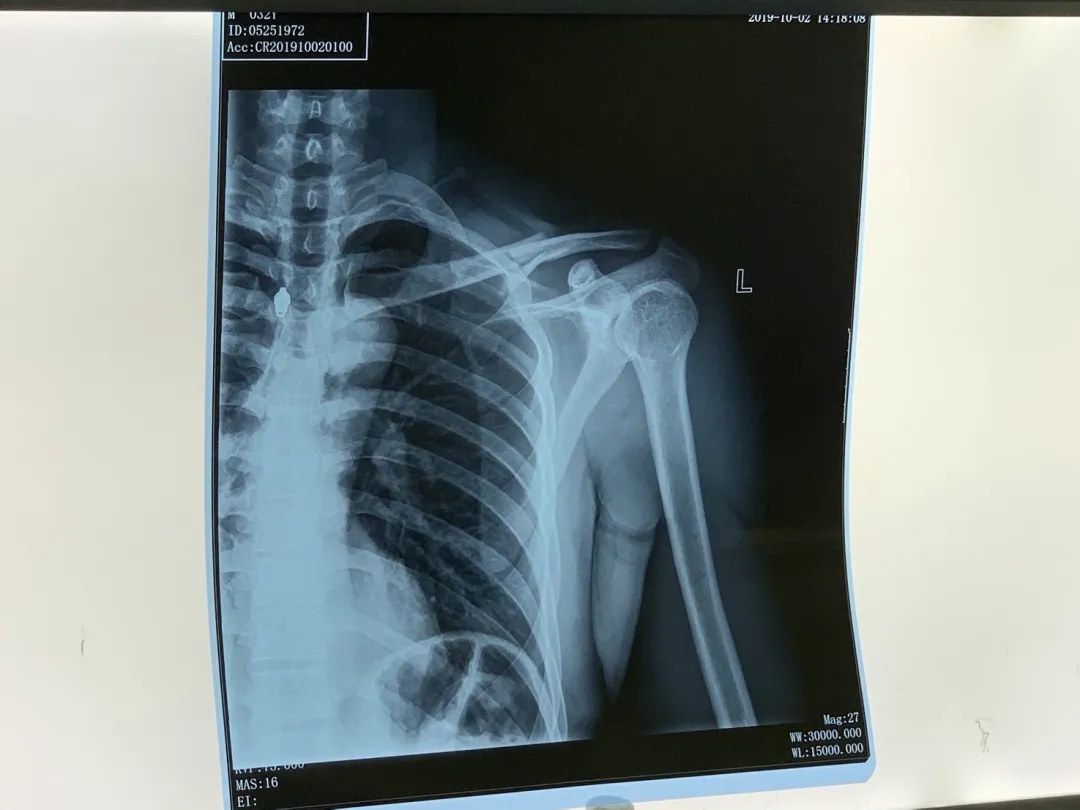

拿到急诊X线片的结果,我自己都能看出来左边锁骨是童叟无欺地断了,成了三截。我右手扶着左臂,呲牙咧嘴地拿着片子回去找医生,等待接下来的安排。

左侧锁骨断了丨作者供图